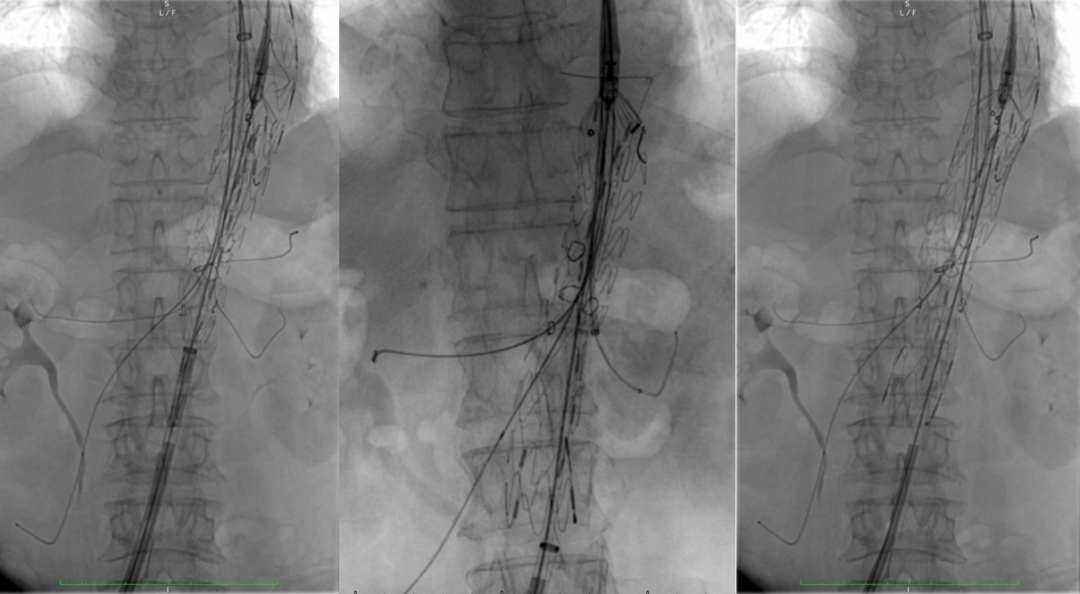

治疗方案:PMEG拓展近端锚定区,重建CA、SMA、RRA和LRA

35-14-140mm分叉型支架,缝制内分支并固定,RRA、LRA:5mm Viabahn,CA、SMA:7mm Viabahn

分支预置导丝,回装支架

右侧:16-16-140mm Excluder髂腿;

左侧:16-16-120mm Excluder髂腿